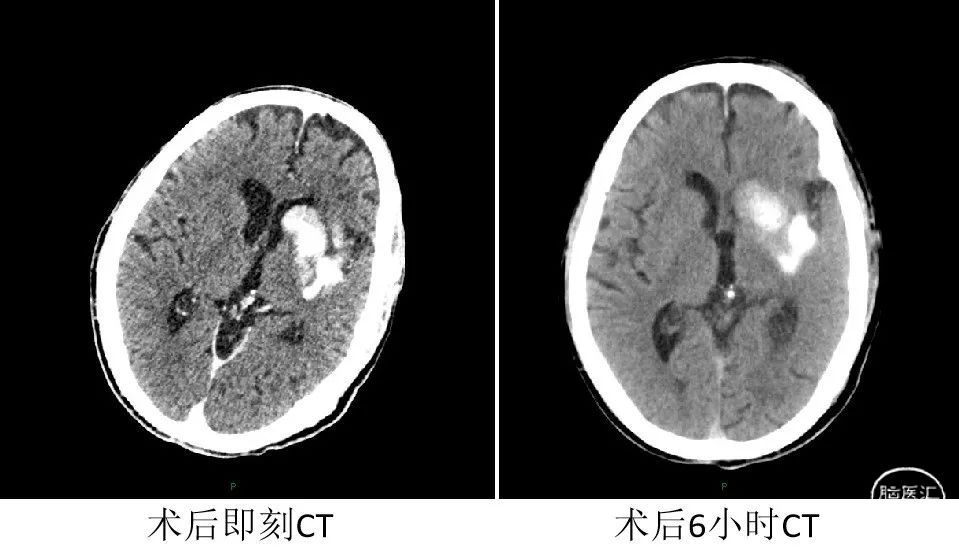

术后6小时患者状态:神智清醒,构音不清,右侧肢体肌力恢复至2级,NIHSS评分9分。

术后24小时复查CT提示未见出血,改为阿司匹林+波立维双重抗血小板聚集治疗。